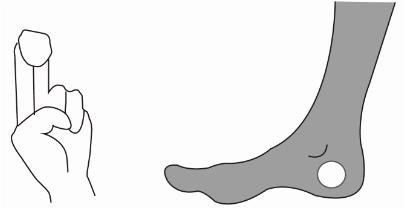

一、跟骨密度儀檢測時,耦合劑的涂抹位置

在受檢者的足跟上涂抹耦合劑時,是為了除去油囊和受檢者的足跟之間殘留的空氣,在足跟上涂抹充分的耦合劑,確保受檢部位與油囊接觸部位完全被覆蓋。

不正確超聲耦合劑用量不充分且位置